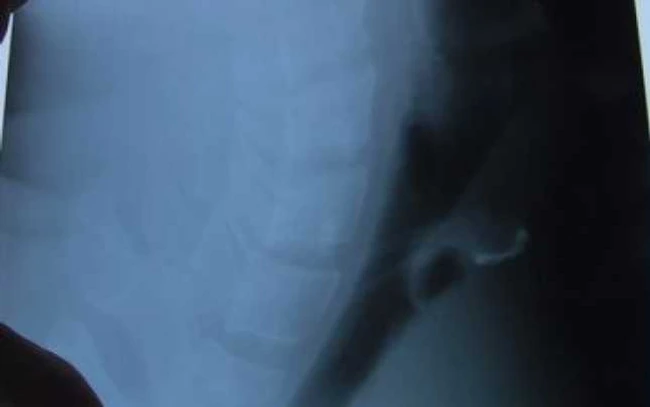

Un bărbat de 39 de ani din comuna ieşeană Ţigăneşti şi-a înghiţit proteza dentară care i-a fost montată provizoriu de medicii stomatologi

Proteza i s-a oprit în zona gâtului şi, după ce a stat 12 de ore cu ea încercând să o scoată, bărbatul a ajuns la Spitalul de Urgenţe din Iaşi.

„Este un pacient norocos că nu a dezvoltat alte complicaţii, în special respiratorii“, a declarat Tudor Ciuhodaru, coordonatorul Unităţii de Primire Urgenţe din cadrul Spitalului "Sf. Ioan".